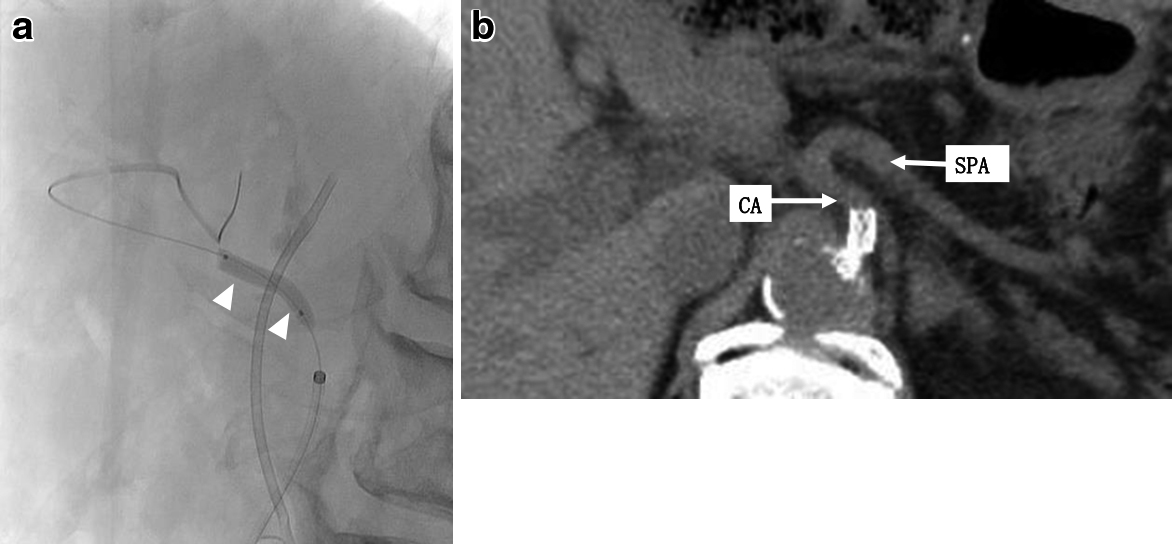

SMA造影で肝動脈や脾動脈が描出され,CAからの造影では呼吸変動を伴わないCA起始部の狭窄を認めた(Fig. 3a, b).

Preoperative angiography. a: The hepatic and splenic arteries were visualized via the SMA. b: There was severe stenosis into the celiac artery (arrowhead).

CA起始部の狭窄点を確認し,呼吸変動にて狭窄の増悪がないことを確認したうえで,径6 mm×長さ18 mmの血管ステントを腹腔動脈内に留置した(Fig. 4a, b).ステント留置後,バイアスピリン錠(100 mg)内服による抗凝固療法を再開した.

SMA angiography and preoperative CT after replacement of the stent. a: Vascular stent was replaced in the celiac artery (arrowheads). b: Stent was replaced into the celiac artery.